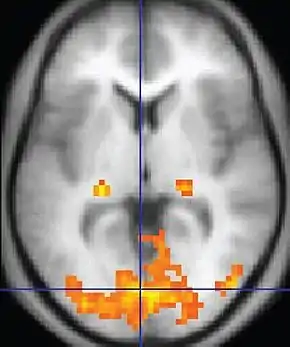

| Functional MRI (fMRI) | Blood-oxygen-level dependent imaging | BOLD | Changes in oxygen saturation-dependent magnetism of hemoglobin reflects tissue activity.[90] | Localizing brain activity from performing an assigned task (e.g. talking, moving fingers) before surgery, also used in research of cognition.[91] | ![]() |